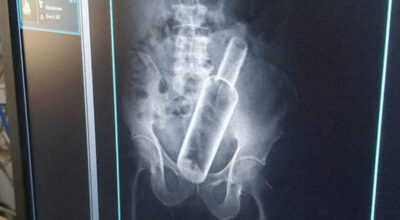

६१ वर्षीय जमनसिंहको पेटमा भेटियो रक्सीको बोत्तल